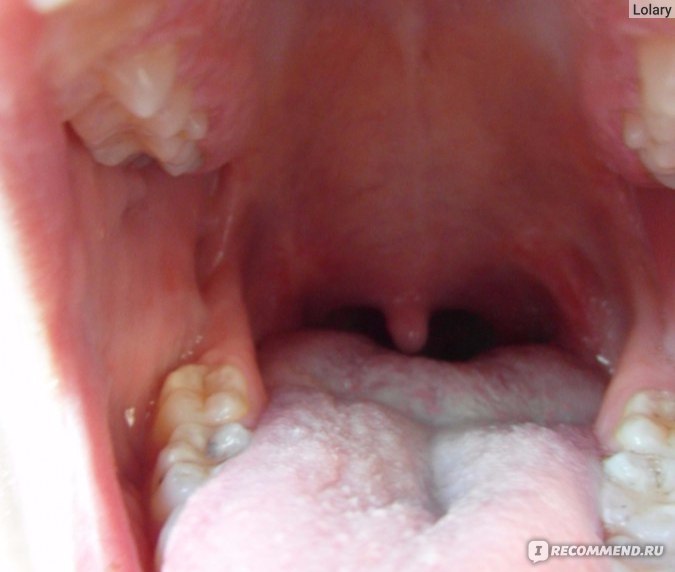

Причины хронического тонзиллита (постоянно увеличенных миндалин) у детей и взрослых

- Частые острые воспалительные процессы в лимфоидных образованиях (ангины, ОРВИ) приводят к:

- изменению тканей миндалин – трансформация лимфоидной ткани в соединительную;- потере способности к самоочищению;

- сужению и деформации лакун;

- формированию застоя содержимого лакун и образованию гнойных пробок;

- образованию рубцов, которые полностью закрывают некоторые лакуны, а инфекционное содержимое находится внутри них.

Иммунная система претерпевает значительные изменения, поэтому хронический тонзиллит относят к аутоиммунным заболеваниям. Измененные миндалины перестают выполнять свою функцию и превращаются в хронический источник инфекции. Малейшая инфекционная атака извне вызывает клинически тяжелые ОРВИ, ангины, а постоянное присутствие патологической микрофлоры приводит к развитию резистентности к антибиотикам и противовирусным препаратам, в с каждым разом усложняя лечение ЛОР-заболеваний.